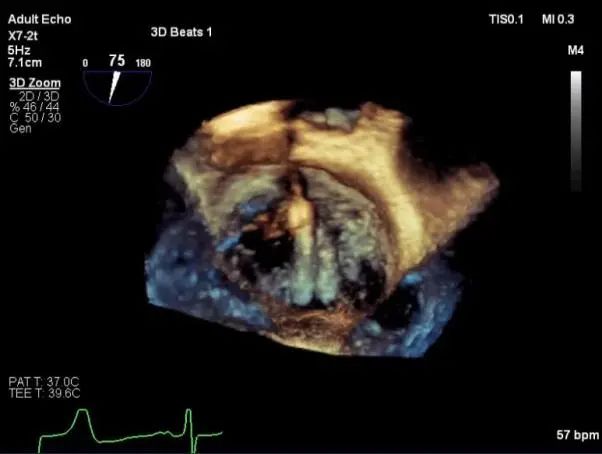

三维超声心动图显示第一枚XTR夹子释放,残余返流主要位于外侧

三维超声心动图显示第二枚XTR夹子释放